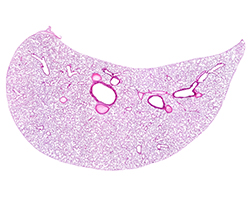

Sistema Endocrino

Sistema Endocrino

Hipófisis, tiroides, paratiroides, suprarrenal, I. de Langerhans y pineal.

(14 preparaciones) -